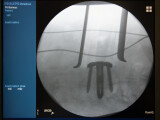

Galerie: Olomoucký lékař navrhnul náhradu ploténky. Pomáhá už stovce pacientů

zdroj: FNOL